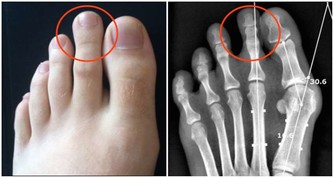

緩解足底筋膜炎的四種練習 這種「腳後跟劇痛」絕大多數與「足底筋膜炎」有關,腳跟承受全身重量,長年伸展擠壓之後,易造成發炎現象,由於疼痛感如針刺般,也多稱為「足跟痛」或「跟骨骨刺」,患者除適當休息外,應進行適量的伸展運動,根據《FootLogics》報導指出,以下三種簡單練習,澳州骨科醫師及物理治療師建議足底筋膜炎患者在家練習,一般民眾鍛鍊也有預防作用: